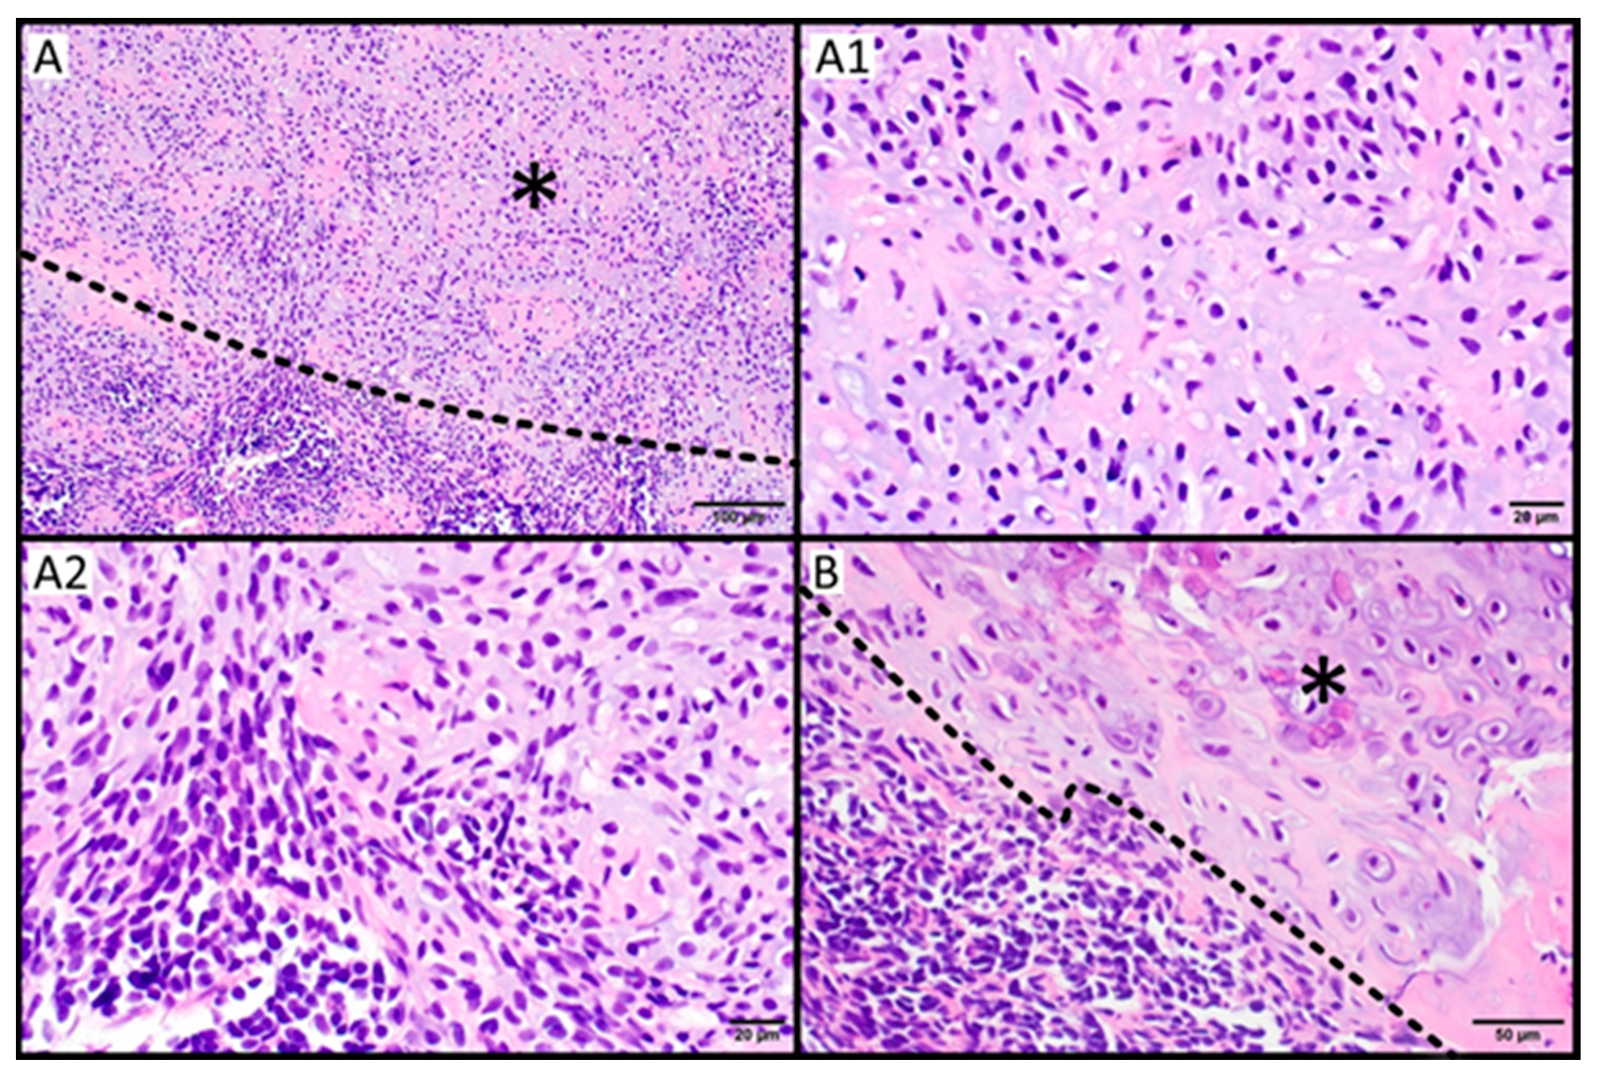

2.4. Histopathology